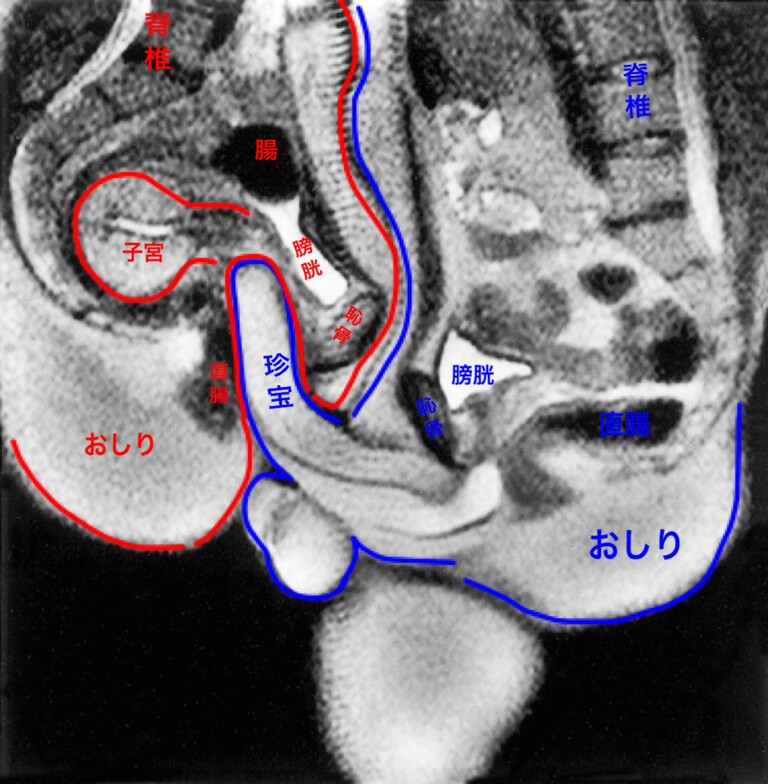

45分間にもおよぶMRIでの撮影の結果、論文に掲載された画像がこれ。右側にいるヤップ氏の

ペニスが、しっかりとサリベス氏の膣に挿入されていることがわかります。この画像から、

ヴァン=アンデル氏は「挿入時のペニスはダ・ヴィンチが描いた断面図のように直線的ではなく、

実際のところブーメランのように曲がっている」ことなど、これまで知られていなかった事実を発見できました。